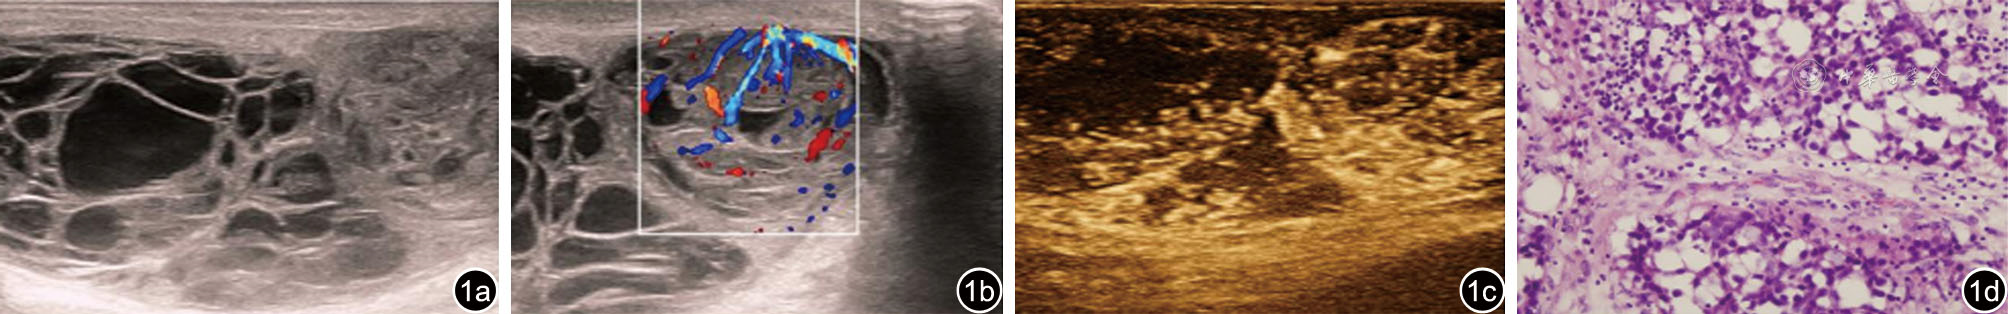

图1 睾丸精母细胞瘤二维及血流图像、超声造影图像、病理图片 图a为睾丸肿物二维图像,睾丸增大,内见囊实性肿物,上方以囊性为主,下方以实性为主;图b为彩色多普勒图像,肿物分隔及实性部分见丰富血流信号;图c为超声造影图像,肿物分隔及实性部分见网格样强化;图d为精母细胞瘤病理图片(HE,×400)